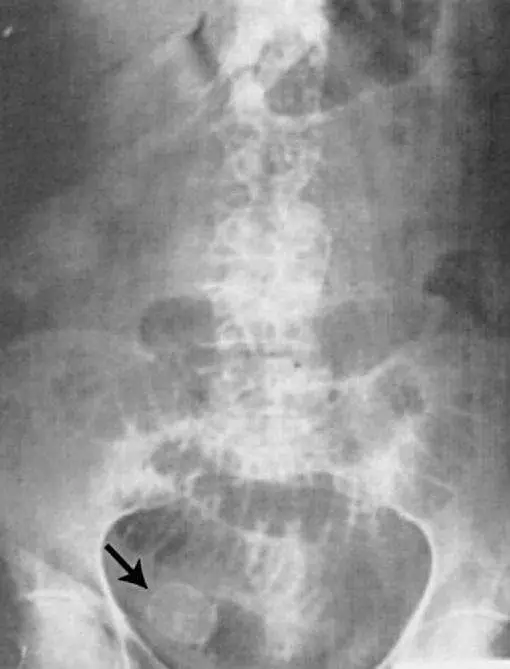

陳奶奶今年 75 歲,胃手術後長期右上腹疼痛,但陳奶奶並不以為意,有天突然腹脹、噁心嘔吐到急診就診,腹部 X光(如下圖)檢查發現右下方有一顆 radiopaque (箭頭處)的 mass ,下列何項診斷最符合陳奶奶的臨床表現?

膽石性腸阻塞(gallstone ileus)是一種罕見但危急的機械性腸阻塞,成因為膽結石經膽腸瘻管(cholecystoenteric fistula)移行至腸道後嵌頓,多見於老年女性及有膽囊病史者。本題患者有胃部手術史,長期右上腹疼痛(疑似慢性膽囊炎/膽石症),突發腹脹、噁心嘔吐,腹部 X 光在右下方見一 radiopaque mass,高度符合此診斷。

本題腹部 X 光(平片)所見如下:

- 整體腸道:可見中腹部多處腸管擴張,伴有氣液平面(air-fluid level),提示機械性腸阻塞(mechanical bowel obstruction)。

- 右下腹箭頭處(右髂窩):可見一枚橢圓形 radiopaque 緻密影,邊界尚清晰,為嵌頓於腸道(多為迴腸末端或迴盲瓣)的鈣化膽結石(ectopic calcified gallstone)。此位置為膽石性腸阻塞最常見的結石卡頓部位。

- 上腹部:正常膽囊區影像消失,需注意是否有 pneumobilia(膽道積氣),為膽腸瘻形成的間接證據。

此 X 光呈現 Rigler 三徵(Rigler's triad) 的關鍵成分之一:異位 radiopaque 膽結石(ectopic radiopaque gallstone in right iliac fo